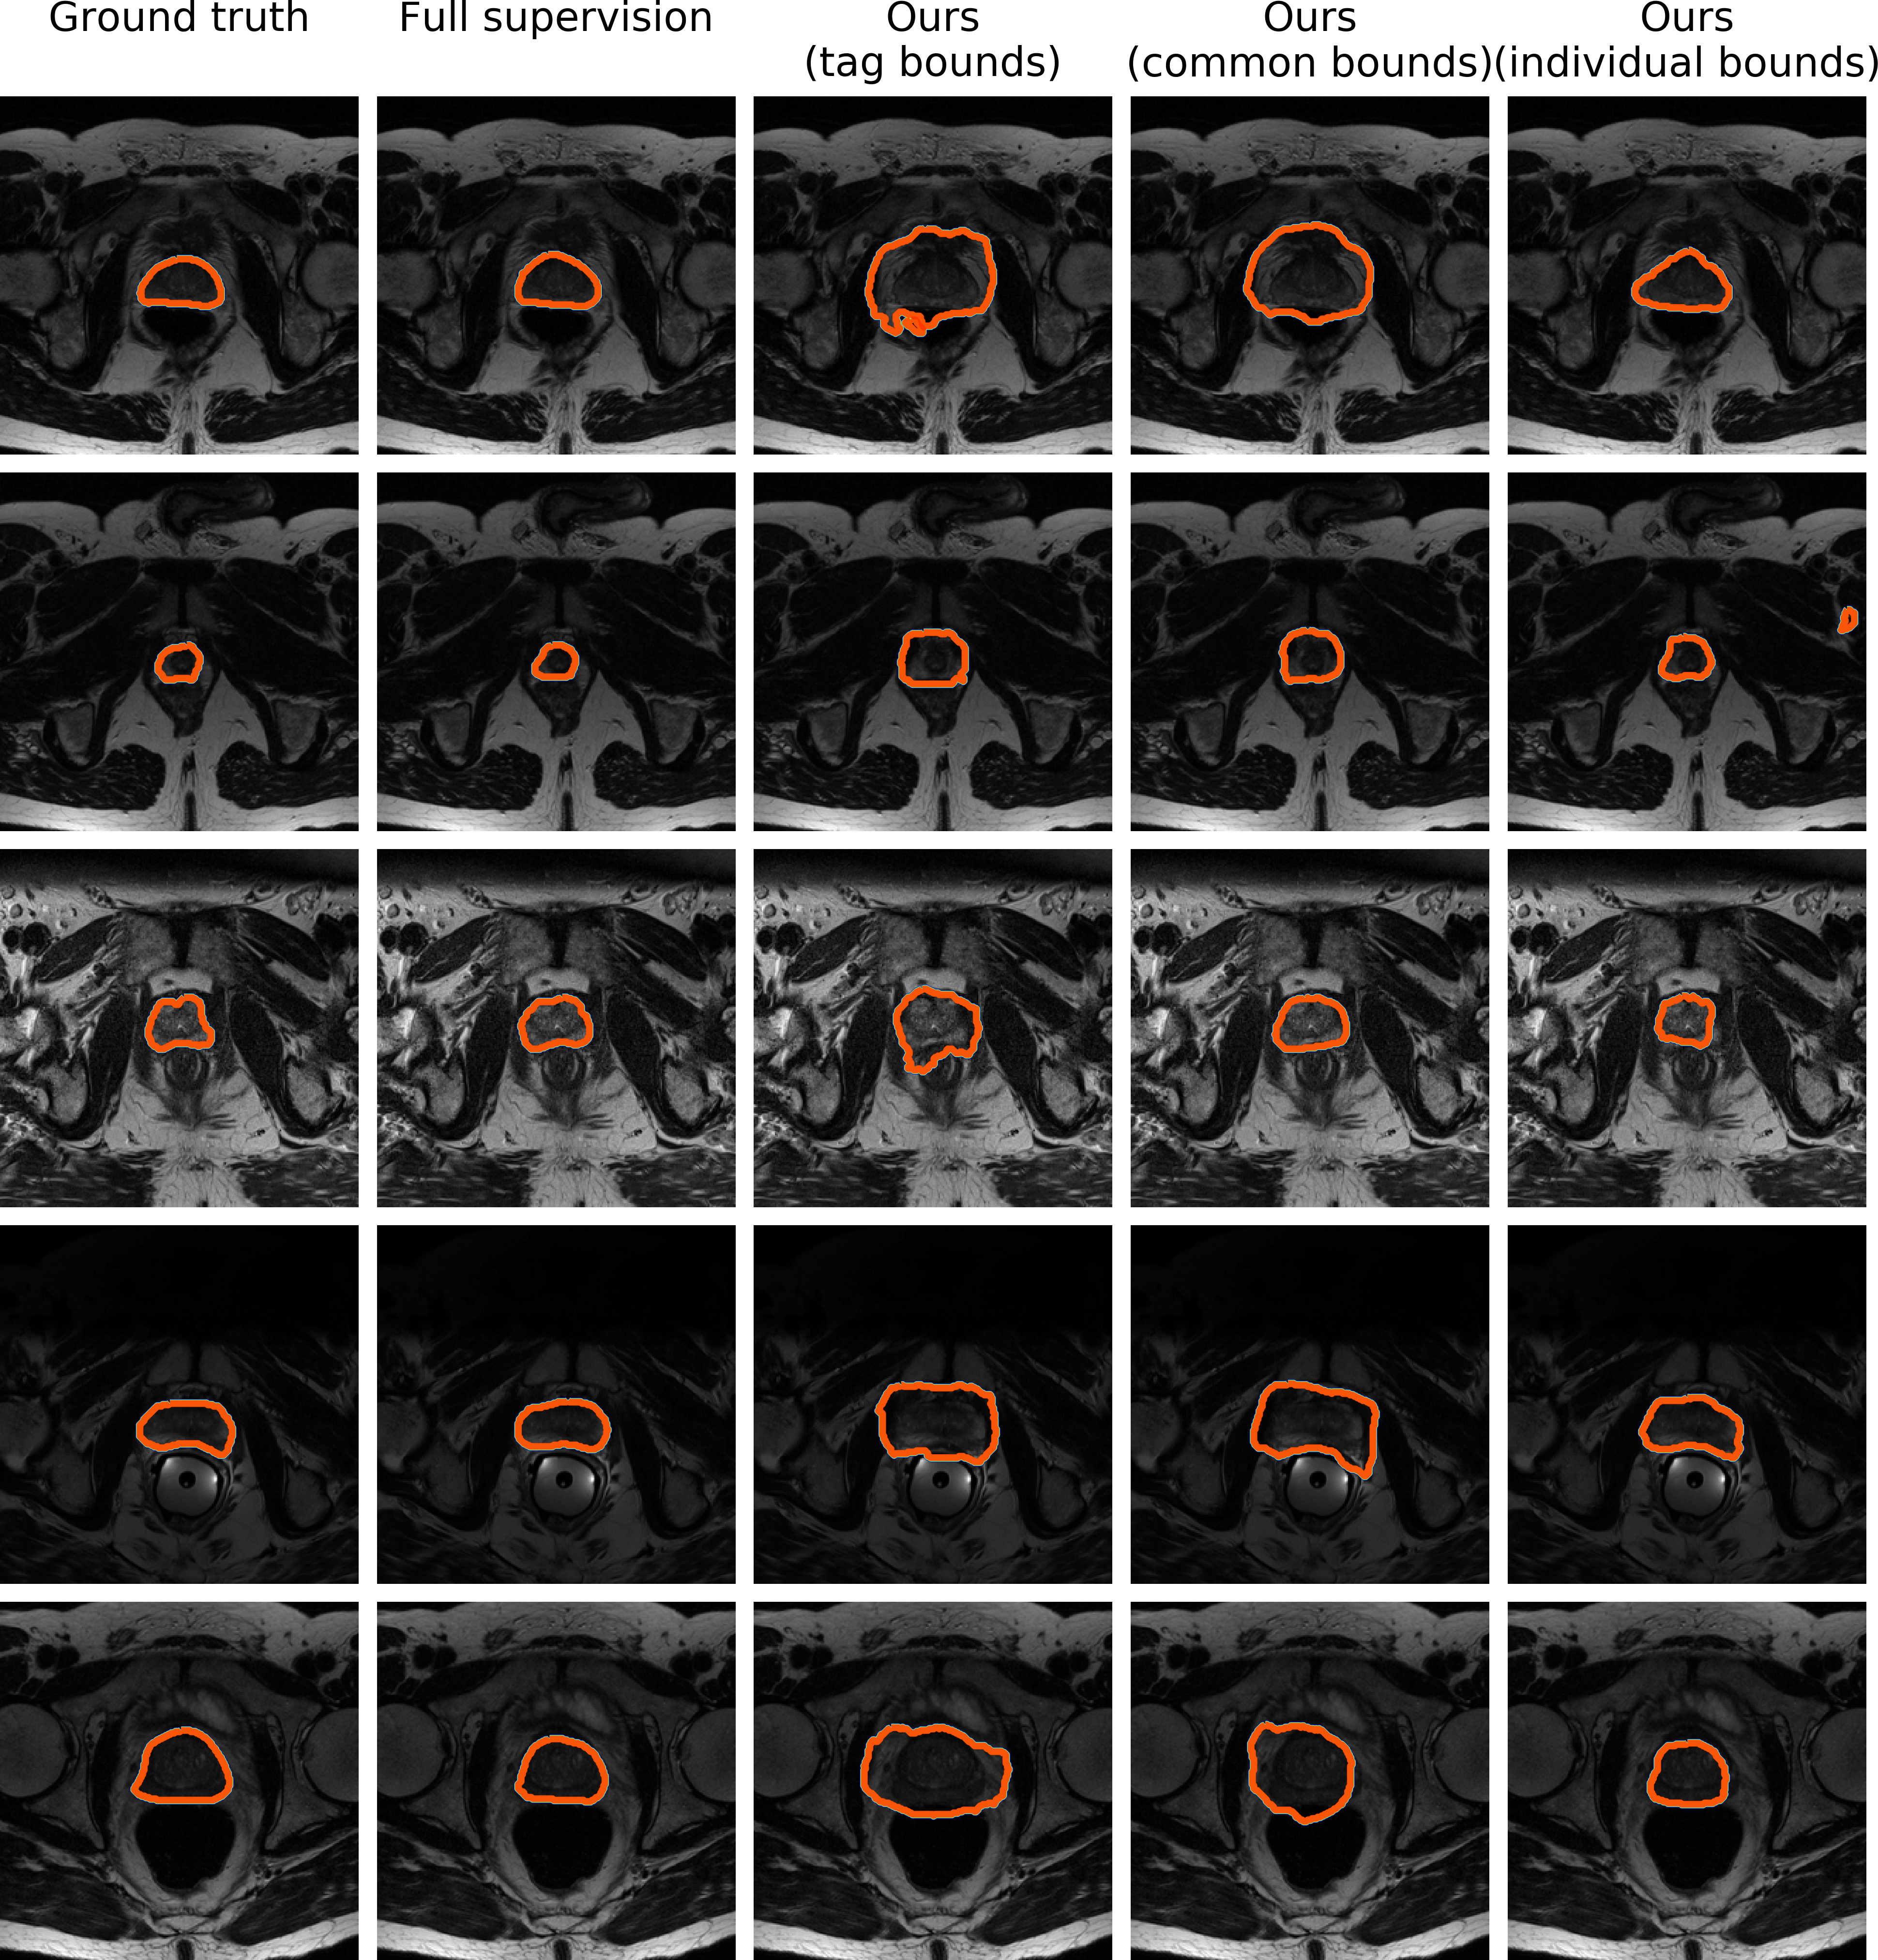

Vertebral-body segmentation task

In this case, we visualize the results of full supervision, tag bounds, common bounds and individual bounds. In line with results reported in Table 3, we can visually observe the gap in performances between each setting, which clearly highlights the impact of the different values of the bounds during the optimization process. Using only tags, the network learn to roughly locate the object. When size bounds are included as common size information, the network is able to somehow learn the boundaries, but only for object shapes that are within the standard variability of a typical vertebral body shape. As it can be observed, the model fails to segment the unusual shapes (last three rows in Figure 6). Lastly, a network trained with individual sizes is able to better handle those cases, while still being imprecise on some regions.

Refer to caption

Figure 6: Qualitative comparison using examples from the VB dataset. Each column depicts segmentations obtained by different levels of supervision, whereas each row represents a 2D slice from different scans (Best viewed in colors).